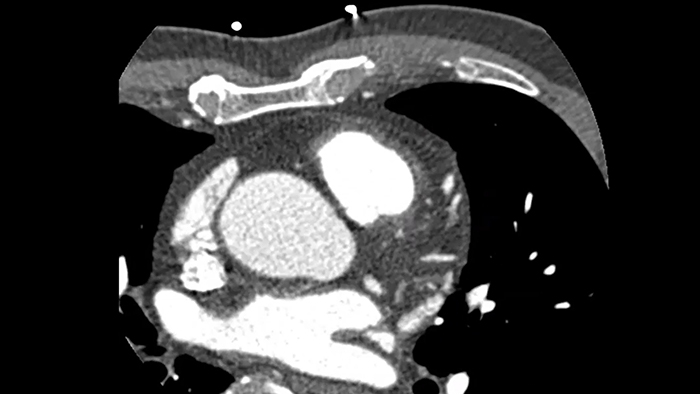

Overcome cardiac imaging challenges

Motion-free cardiac imaging improves image quality at high heart rates

ContinueAdvanced motion-compensation reconstruction for motion-free cardiac scanning with improved coronary analysis